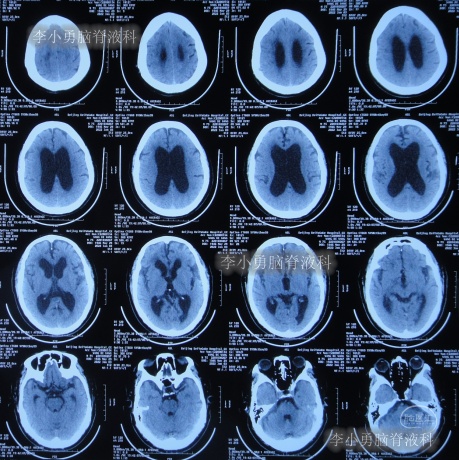

2021年4月14日(腰大池腹腔分流术后17天),头痛腿沉再次加重,复查头部CT示硬膜下血肿(图-3)。

图-3:2021年4月14日头部CT

2021年4月16日(腰大池腹腔分流术后19天),因意识变差,查头部CT(图-4)后,急诊进行了硬膜下血肿引流术,并升高分流泵的压力200。

图-4:2021年4月16日头部CT